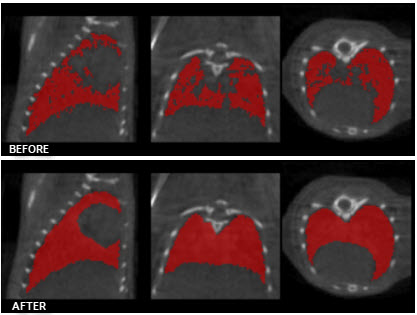

Low-pass Smoothing

Use the Low-pass Smoothing filter to remove jagged surfaces from manually created ROIs. The amount of smoothing can be controlled with the Low-pass radius parameter. Smaller radii will result in smoother ROIs.